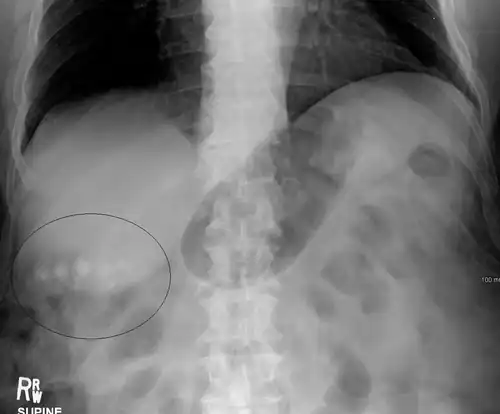

Large gallstones can potentially erode through the gallbladder wall and into the neighboring small intestine. This large stone then travels through the small intestine until it is too narrow for the stone to continue, causing a small bowel obstruction. This obstruction often occurs at previous surgical sites or at the ileocecal valve (the portion of the bowel where the small intestine meets the large intestine). The patient presents with the inability to defecate or pass gas, nausea, vomiting, and severe abdominal pain.[14]

Mixed (brown pigment stones) typically contain 20–80% cholesterol (or 30–70%, according to the Japanese classification system).[41] Other common constituents are calcium carbonate, palmitate phosphate, bilirubin and other bile pigments (calcium bilirubinate, calcium palmitate and calcium stearate). Because of their calcium content, they are often radiographically visible. They typically arise secondary to infection of the biliary tract which results in the release of β-glucuronidase (by injured hepatocytes and bacteria) which hydrolyzes bilirubin glucuronides and increases the amount of unconjugated bilirubin in bile. Between 4% and 20% of stones are mixed.[3]

Diagnosis is typically confirmed by abdominal ultrasound. Other imaging techniques used are ERCP and MRCP. Gallstone complications may be detected on blood tests.[2]